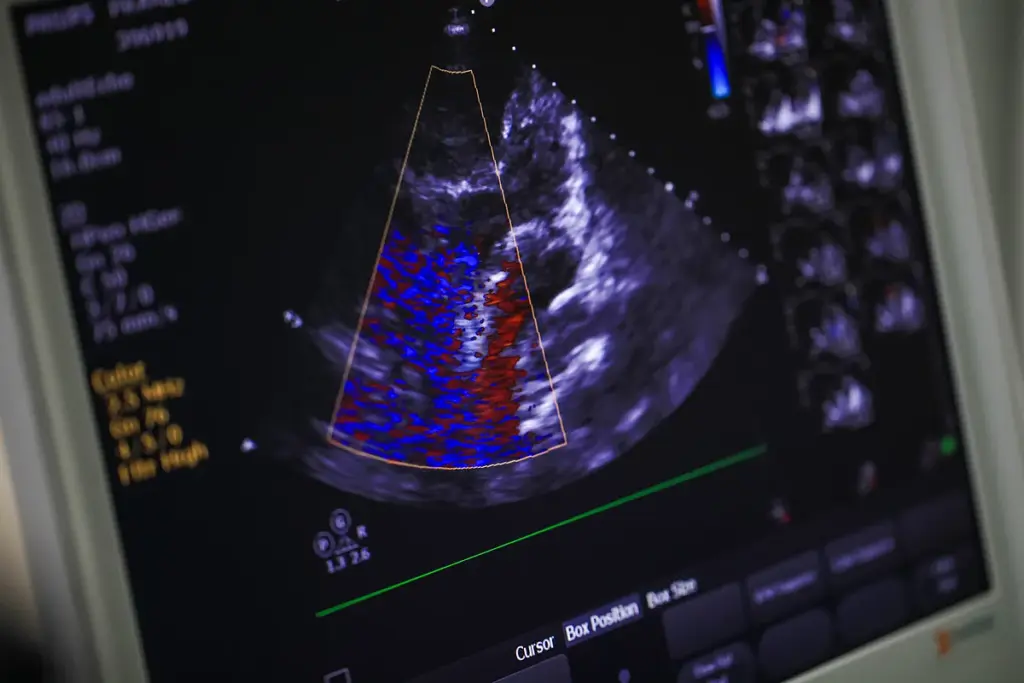

Understanding the Calcium Score Test

A calcium score test gives important insights into your heart artery health. The test is non-invasive and measures calcium in the arteries. This helps assess your risk for heart disease.

Definition and Purpose of the Test

The calcium score test uses CT scans to find and measure calcium in your heart arteries. Its main goal is to check your risk for heart disease by counting the calcium.

Calcium in your arteries shows how much plaque you have. Doctors use this info to see how likely you are to get heart disease. They then suggest ways to prevent it.

How the Test Works

During the test, a CT scanner takes pictures of your heart. It looks at your heart arteries to find calcium. The test gives a calcium score, which shows how much calcium is there.

The test uses low-dose radiation to get clear pictures. This means you don’t need a big, invasive procedure to get this info.